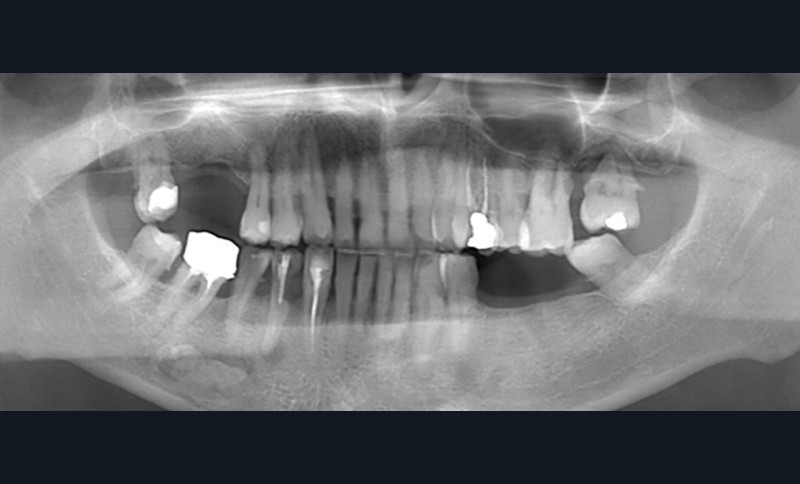

- Quelle anomalie radiologique observez-vous sur cette radiographie panoramique ?

- Comment la nommeriez-vous ?

- Quels diagnostics différentiels pourraient être évoqués ?

- Quels examens complémentaires et/ou quelle conduite à tenir recommanderiez-vous ?

Observations : Outre les constatations habituelles (dents dévitalisées, point sur les 3e molaires, etc.) et outre la calcification des ligaments stylo-hyoïdiens droit et gauche, on observe en regard de la dent 36, au niveau sous-apical, une image radio-opaque arrondie, bien limitée, indépendante des racines. La dent 36 apparaît vitale, indemne de lésion carieuse ou de remaniement péri-apical.

Interprétation : L’aspect évoque en première intention une ostéosclérose idiopathique. Une lithiase salivaire (ou sialolithiase, affection définie par la formation de calculs ou sialolithes) pourrait également être discutée, de même qu’un ostéome périphérique (tumeur bénigne constituée d’os dense normal) en projection sur ce cliché. Toutefois, la morphologie et la localisation sont en faveur d’une forme idiopathique.

Conduite à tenir : Un suivi radiologique régulier est à préconiser au moyen d’une radiographie panoramique tous les deux ans. Aucun examen complémentaire n’est nécessaire en l’absence d’évolution atypique ou de caractéristiques radiographiques suspectes. Si nécessaire, pour asseoir définitivement le diagnostic, un CBCT peut être réalisé (petit champ : champ 4×4, dose 188mGy.cm², voxel 125 µ).